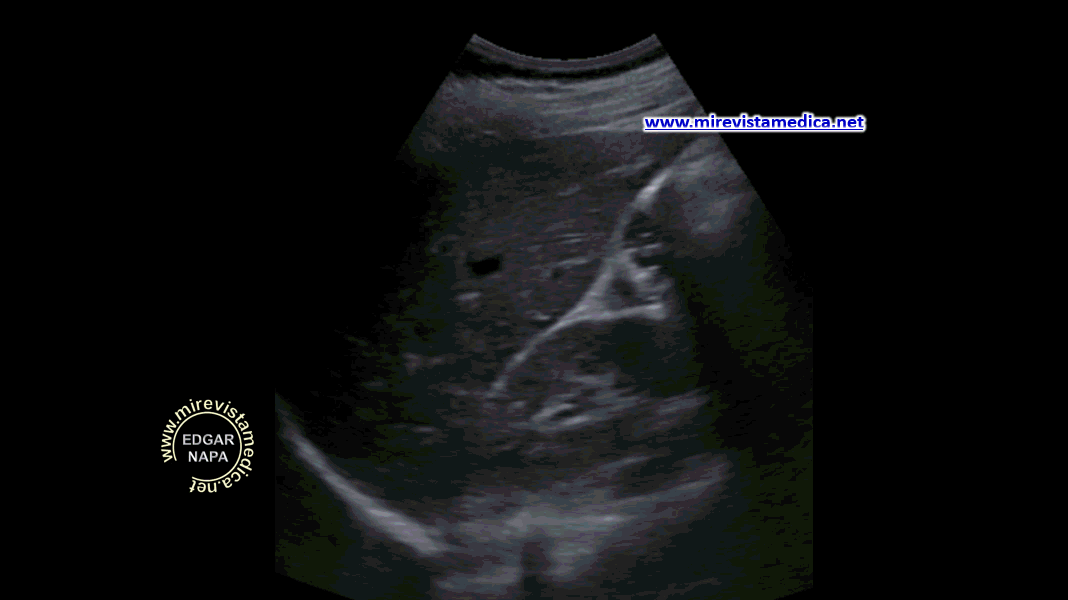

Anatomía imagenológica de la vía biliar